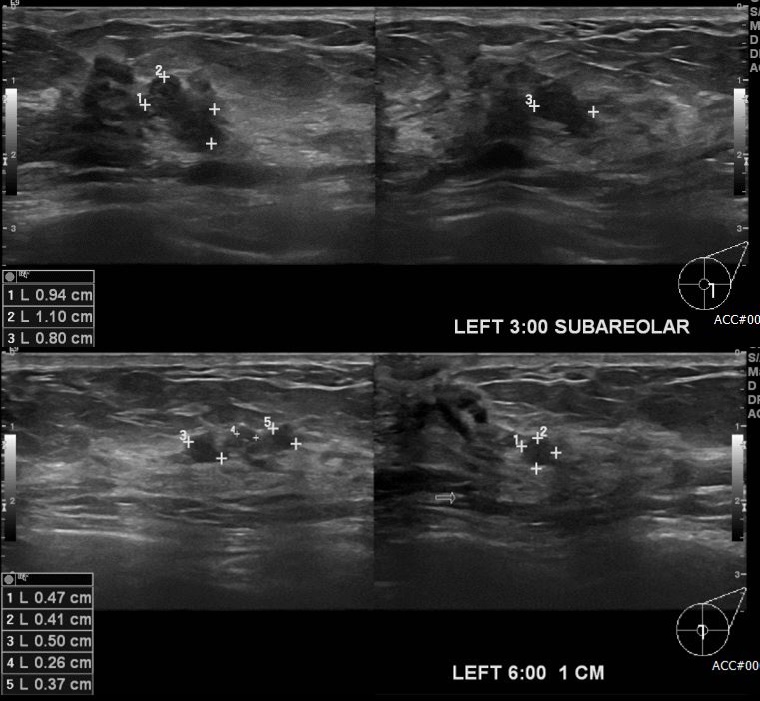

좌측 유방에 분비물로 내원하신 40대 여성 분으로 유방 초음파 시행 후 좌측 3시 유두및과 좌측 6방향에서 1cm 떨어진 거리에 의심 스러운 혹 각각 조직검사 시행하여  좌측 유관암 진단 되었습니다.